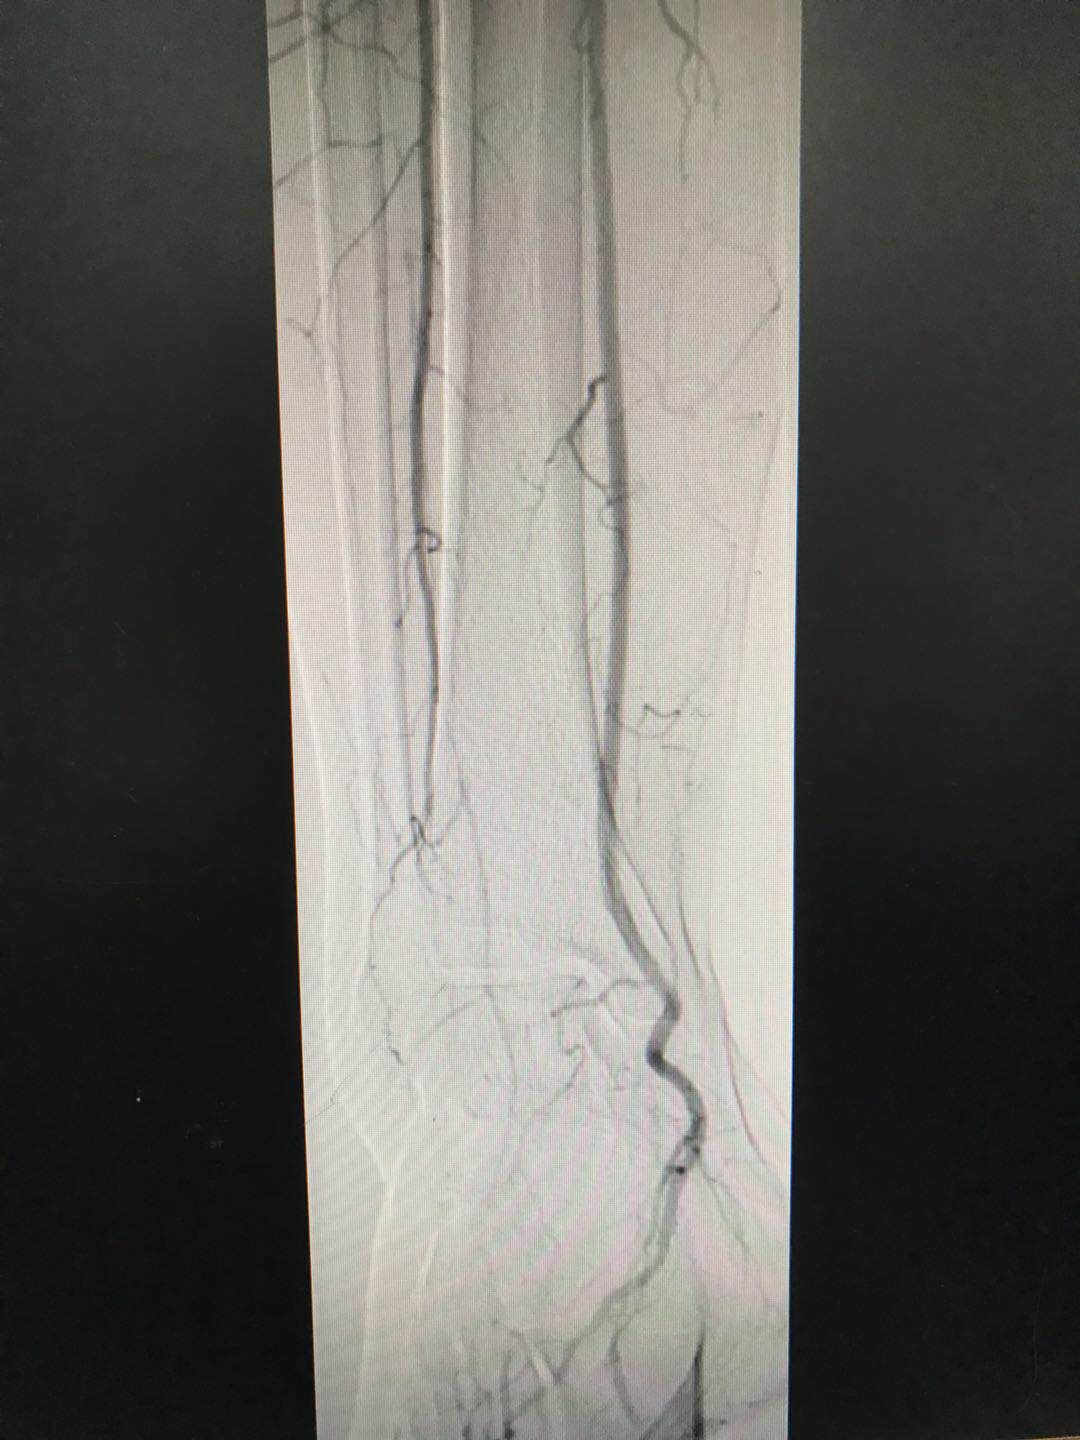

7月24日上午,西安市第九医院内分泌科马磊主治医师与介入科钟勇进主治医师合作,完成内分泌科首例糖尿病下肢动脉硬化闭塞症患者下肢动脉造影术。术中显示该患者右侧胫前动脉闭塞,腓动脉远端闭塞,手术过程顺利。通过造影结果,为患者制定了全面的血糖管理和下肢血管病变防治的方案。患者及家属对我院的医疗服务和诊疗技术水平给予了高度的赞扬。